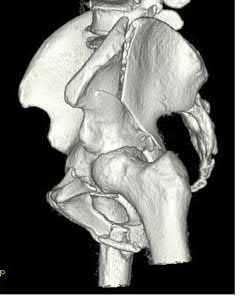

A 26-year-old male with a BMI of 37 is involved in a motor vehicle collision and requires extrication. During evaluation in the trauma bay, he becomes hemodynamically unstable and is found to have the injury shown in Figure A, as well as an associated bladder injury. Which of the following statements regarding the patient's injury is true?

The patient has an APC pelvis injury. Increased BMI has been associated with a higher risk of infection after surgical intervention of pelvic and acetabular fractures.

Pelvic fractures result from high-energy mechanisms and frequently require surgical intervention. When performing open procedures in the pelvis, the risk of infection is of concern. Elevated BMI has been shown to be the most

important risk factor for infection. Other risk factors include prolonged operative time, prolonged ICU stay, increased red blood cell transfusions, leukocytosis, Morel-Lavallée lesion, and associated genitourinary and abdominal trauma. Preoperative angioembolization as a risk factor for SSI remains controversial but is thought to be associated with embolization and not with angiography itself.

Iqbal et al. performed a retrospective study on surgical site infection following fixation of acetabular fractures. They found that prolonged operation time, increased BMI, prolonged ICU stay, larger amount of packed red blood cell transfusions, and associated genitourinary and abdominal trauma were associated with surgical site infection following acetabular fracture fixation.